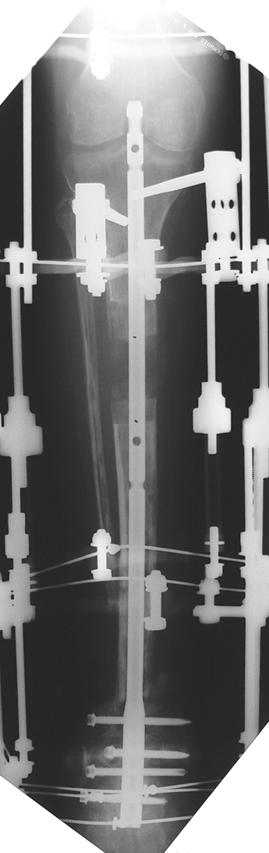

Recently, ilizarov techniques which is basis depend on distraction osteogenesis , bone segment transport or acute shortening after the resection at the site of pseudarthrosis combined with lengthening at another level of bone have been used. These treatment techniques may include some advantage for problems of infection, leg-length discrepancy, soft-tissue loss, and joint contracture.

Management of Stiff Hypertrophic Nonunions by Distraction Osteogenesis – A Report of 16 Cases

Tibial nonunion